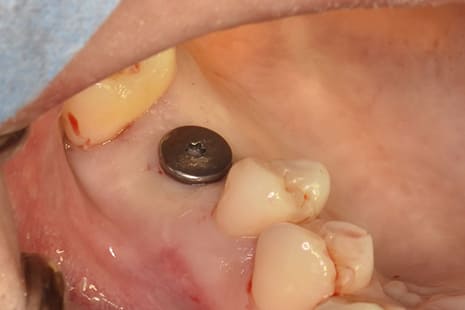

フラップレス術式インプラント治療とは、歯肉を切らずに行う無切開手術です。

このフラップレスインプラント治療は、CTや3Dシミュレーションで最適な位置を確定し、手術用ガイドを用いて歯肉を切らずにインプラントを埋入する低侵襲で身体に優しい治療法となります。

ガイデットサージェリーを使用したフラップレス術式によるインプラント治療の流れ。

パンチングによる歯肉の剥離

ガイデットサージェリー

インプラント埋入

縫合しない低侵襲な術後